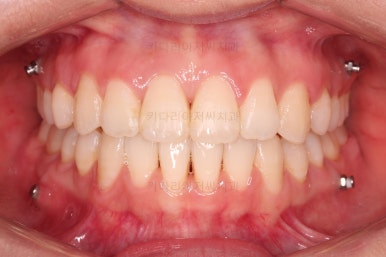

종료 시 사진입니다.

중앙선, 교합, 치아배열 모습 모두 양호해졌습니다.

부산교정잘하는치과 전후 비교해 보겠습니다.

치열도 당연히 좋아졌지만 웃을 때 보이는 치열도 매우 예뻐졌습니다.

입매도 본인이 원하는 수준으로 딱 멈춰드렸고, 적절하게 자연스럽게 약간 들어가고 마무리가 되었습니다.

전반적으로 매우 만족하신 치료가 되었습니다.